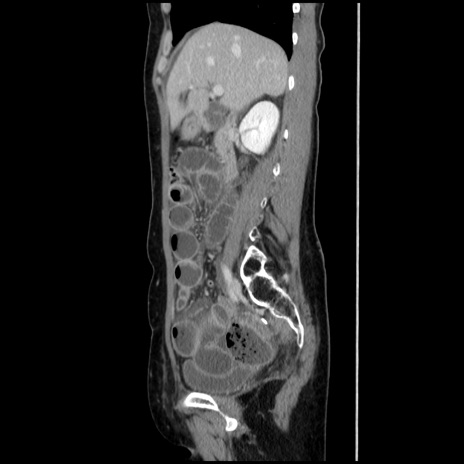

症例32(矢状断像)

【症例】40歳代 女性

【主訴】上腹部痛、嘔気・嘔吐

【現病歴】約9時間前頃から急に上腹部痛、嘔気、嘔吐が出現。改善しないため救急要請。

【既往歴】子宮頚癌(広汎子宮全摘術、放射線療法)、腸閉塞

【身体所見】腹部:平坦、軟、腸雑音亢進、上腹部を中心に腹部全体に圧痛あり。

【データ】WBC 8400、CRP 0.03

冠状断像